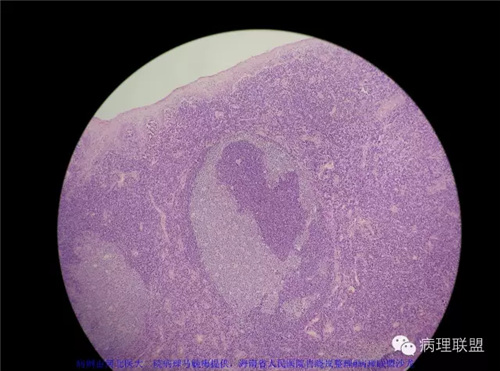

M/42,发现右扁桃体肿物。大小0.8*0.6*0.3cm。

【病理联盟】扁桃体病变中的“滤泡溶解”现象